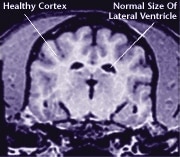

Comme le reste de l’organisme, le cerveau est affecté par le processus de vieillissement. Les dommages subis par les cellules du cerveau peuvent occasionner des changements de comportement et une perte de vivacité chez votre chien.

L’important, c’est de se rappeler que le vieillissement fait naturellement partie de l’existence de votre chien. La moitié des chiens âgés de huit ans et plus commencent à montrer des signes de vieillissement du cerveau, et à mesure qu’ils vieillissent, ils peuvent se mettre à agir différemment. Grâce aux progrès de la médecine et de la nutrition animale, une alimentation appropriée et les conseils d’un vétérinaire peuvent aider à limiter les effets du vieillissement du cerveau chez votre chien et à maintenir son niveau d’activité.

Le vieillissement a un effet néfaste sur l’organisme d’un chien en général, et sur son cerveau en particulier. Au cours des dernières années, les chercheurs ont avancé à pas de géant dans la compréhension du processus de vieillissement. De nombreux experts s’entendent aujourd’hui pour dire que le vieillissement est principalement causé par l’action de molécules d’oxygène instables appelées radicaux libres. À mesure que le cerveau vieillit, les radicaux libres endommagent ses cellules. Même si des facteurs environnementaux peuvent être à l’origine de certains radicaux libres, c’est le métabolisme propre de l’organisme qui produit la majorité d’entre eux.

Le processus de vieillissement s’attaque à tous les systèmes et organes de l’organisme canin, y compris le cerveau. Il en résulte une perte des fonctions cérébrales et bien souvent l’apparition de nouveaux comportements qui n’existaient pas quand le chien était plus jeune.

![]() Healthy Older Brain | ![]() Older Brain with Damage |

| MRI scans show loss of brain tissue in affected dogs. Note: MRI scans are not harmful to dogs. | |